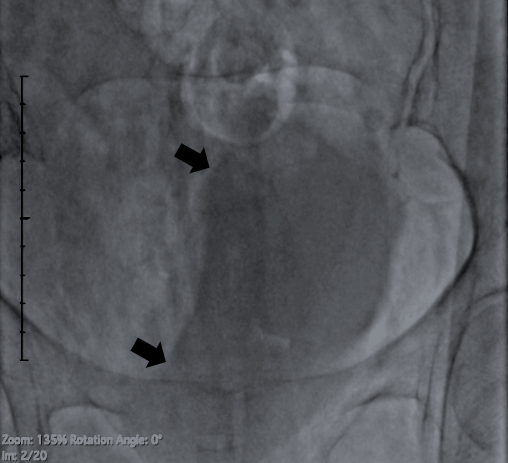

After the completion of PCI, her bladder was checked with fluoroscopy, which revealed gross indentation of the right margin suggesting retroperitoneal hematoma (Figure).

The bladder indentation sign is an early on-table sign to diagnose retroperitoneal hematoma and fluoroscopy of the bladder should be performed routinely to institute prompt treatment.